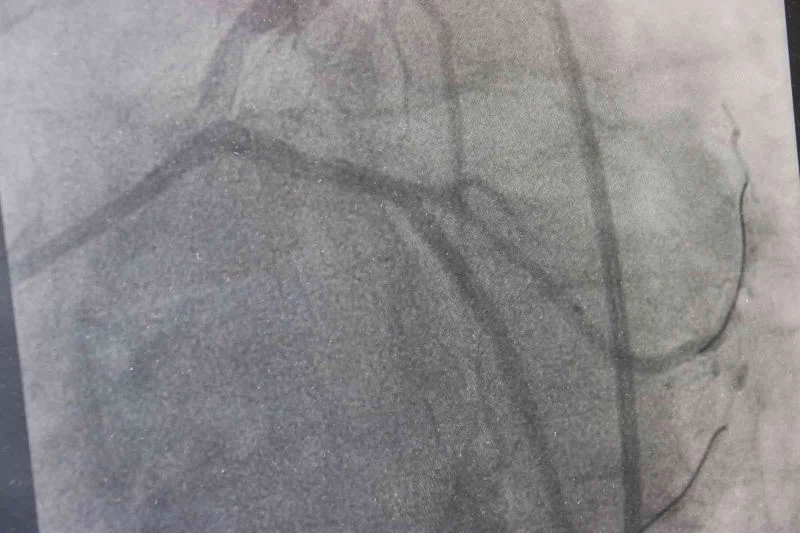

1911’den beri hayatımıza giren trans yağlar, yılda 500 binden fazla insanın ölümüne neden olduğu tespit edildi. Özellikle kalp krizi riskini artırdığı belirtilirken, Kardiyoloji uzmanı Doç. Dr. Serkan Akdağ, çocuklarda ve gençlerde ciddi tehlike arz ettiğini ifade etti.

Trans yağların özelliklerinden dolayı endüstride son derece rağbet gördüğünü aktaran Doç. Dr. Akdağ, “Biz, istemiyoruz. Çünkü trans yağlar insan vücudundaki doğal yağ grubundan çok farklı. Trans yağlar özellikle damarın endotel dediğimiz en önemli kısmını bozan bir madde. Dolayısıyla trans yağlar damar yapılarını bozduğu için başta kalp ve beyin olmak üzere vücudun birçok organına zarar vermekte. Bununla beraber birçok kanserin oluşumuna yol açabilmekte. Obeziteye, şeker ve kolesterol değerlerimizi artırabilmekte. Bu nedenler dolayı biz, trans yağların kullanımını istemiyoruz. Trans yağlar 1911 yılında maalesef hayatımıza girdi. O günden bugüne giderek tüketimi artmakta” dedi.

Trans yağlarla ilgili şu anda Dünya Sağlık Örgütünün de de devam eden bir projesi olduğunu hatırlatan Akdağ, “Yerine koyma projesidir. Amaç da şu, trans yağların endüstride tamamen sıfırlanması, hiç kullanılmaması. Kullanılacaksa maksimum yüzde 2 oranında kullanılması. Biz, yüzde 2’ninde kullanılmasını istemiyoruz. Çünkü yapılan çalışmalarda bu yüzde 2 bile kullanılırsa bu saydığımız hastalıklara neden olabilmekte. Özellikle kalp krizi riskimiz yüksek oluyor trans yağlarla ilgili. Yapılan bir çalışmada günde 5 gram üzerinde trans yağ kullanımının kalp krizi riskini yüzde 25 artırdığı saptanmış. Çocuklar özellikle bu fastfood gıda tüketimi bu oranı ciddi bir şekilde artırmakta. Fastfood gıdalarda çok fazla trans yağ kullanılmakta. Bir avuç kızarmış patateste 8 gram trans yağ bulunmakta. Bunun 5 gram üzerinde olması kriz riskini yüzde 25 artırmakta” diye konuştu.